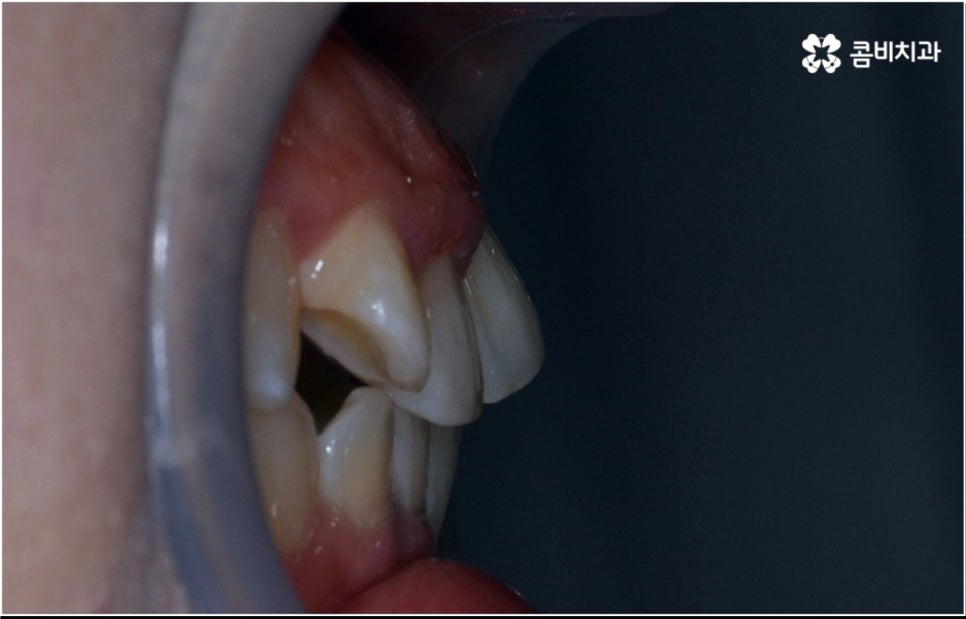

3D CT 등 정밀 검진 기계를 통해 꼼꼼하게 검진을 한 후 환자분들의 부정교합의 종류 및 정도 등에 따라 각자에게 맞는 교정 치료 계획을 수립하게 되는데, 내부 공간이 얼마나 있는지에 따라 발치가 필요한지 아닌지 여부도 달라지고 또 같은 부정교합이라고 해도 사람마다 잇몸 건강이나 치근 상태 등에 따라 잇몸뼈가 벌어지면서 치아가 이동하는 속도, 치아가 자리잡는 양상 등도 모두 달라지기 때문에 성인 치아교정 기간 총 소요 시간은 모두 달라질 수 밖에 없을 거예요.

물론 일반적으로 성장기보다는 잇몸뼈가 굳어진 이후 성인 치아교정 기간 이 길어질 수 밖에 없으나 이 역시 케이스별로 달라질 수 있어요. 예를 들어 만약 임플란트를 심으려고 할 때 공간이 없거나 주변 치열이 삐뚤어져서 어려움이 있기 때문에 하는 교정이거나 앞니 일부가 조금 벌어지고 살짝 각도가 앞으로 나와 있는 등 별다른 골격적 문제 없이 기능성 및 심미성을 보다 개선해 주기 위해서 하는 교정의 경우는 부분 교정으로 진행하기 때문에 보통 발치 과정도 포함되지 않고 성인 치아교정 기간 도 6~8개월 정도로 보다 빠르게 끝날 수 있습니다.

하지만 부정교합의 정도가 심하거나 골격적 문제를 바로잡아 주어야 하는 경우는 전체 교정을 진행해야 하기 때문에 (환자분들마다 다르지만) 평균적으로 18~36개월 정도의 성인 치아교정 기간 이 소요되며, 중장년 성인분들 중에 잇몸 질환 등으로 구강 건강이 약해져 있는 분들의 경우에는 더욱 환자분들의 상황에 맞게 필요한 치료를 병행하면서 무리하지 않은 진행을 해야 하기 때문에 전체 기간이 좀 더 늘어날 수 있어요.